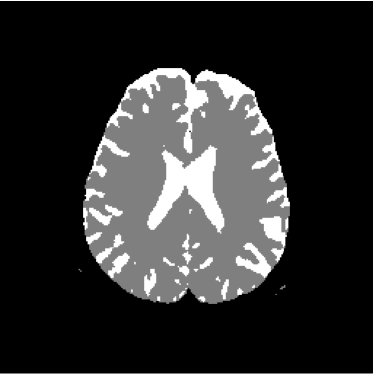

Figure 15: Ground truth volume generated by polynomial net classification

Consequently, the measured similarities between the results obtained by the use of 4-degree and 3-degree polynomial classification related to the 2-degree classification were 0.9816 and 0.9904, respectively. Therefore, we have chosen the result obtained by the 2-degree polynomial classification.

Figure 28 shows 13th slice of classification result obtained by the use of the objective dialectical classifier. Figure 29 exhibits 13th slice of classification result after performing post-labeling, whilst figure 30 shows the entire volume generated by ODC classification.

The training process of ODC algorithm resulted in 6 classes. These classes were reduced to 4 after manual post-labeling, merging 3 classes out of brain region, namely image background, noise and cranial box. The post-labeling is manual because all 3 cited regions are statistically different and, consequently, they are merged due to our interest in classes more related to the brain regions. On figure 29 it is possible to notice that ODC was able to distinguish white matter from the gray matter present in the interface between liquor and white matter.